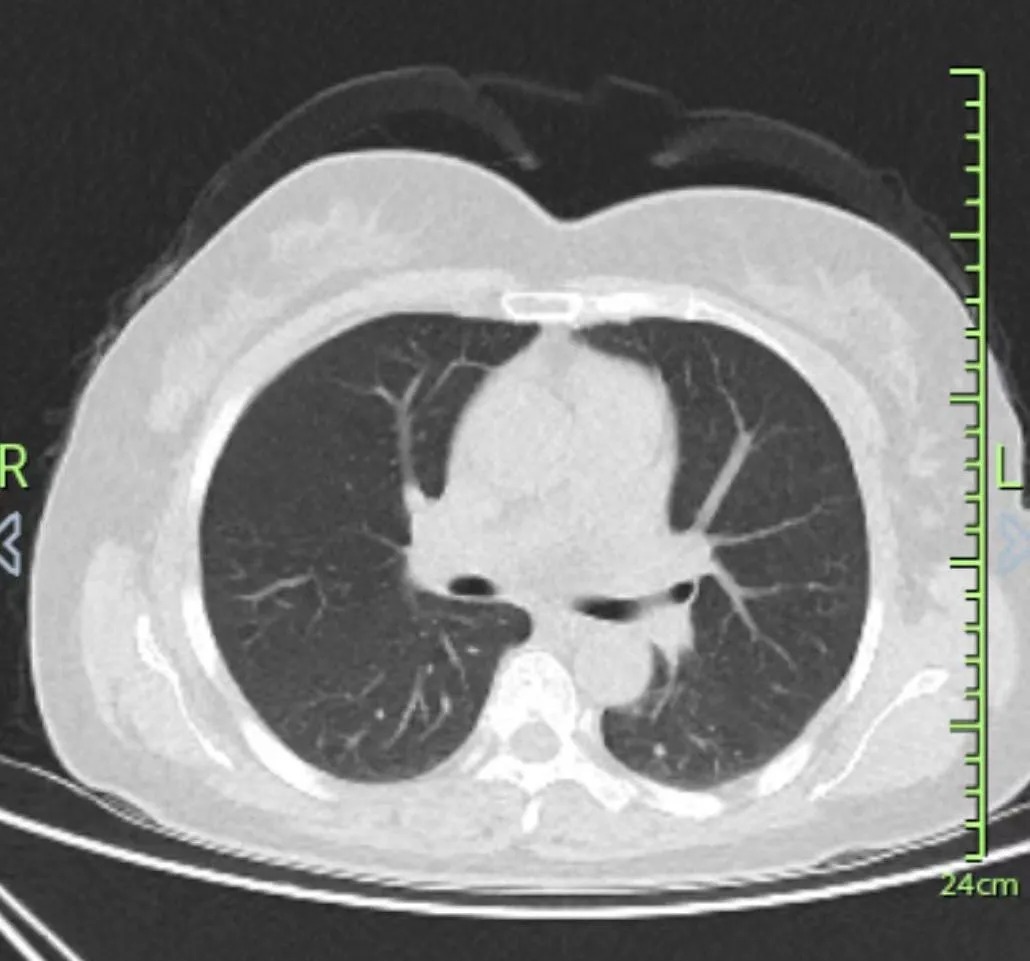

下午3点30分,李主任与刘主任、姚主任等呼吸科专家就三份肺病疑难病例(支气管扩张伴感染一例,肺恶性肿瘤一例、慢性支气管炎加重期一例)进行了深入的研究讨论。家住合肥市包河区的夏大爷,今年72岁,间断性地咳嗽、咳痰、咯血有3年多时间了,自行服药后,症状可缓解,但容易反复发作。直到2024年5月份,才来到外院接受正规专业的治疗,症状缓解。一周前,咳嗽、咳痰、咯血症状加重,在女儿的陪同下,夏大爷来到我院治疗。来自安徽旌德县的巫大爷,今年71岁,肺恶性肿瘤(右侧)4公分,绿脓杆菌感染,同时还有支气管扩张伴感染、呼吸衰竭和纵膈淋巴结肿大,病情较为复杂,治疗起来综合考虑因素较多。来自安徽歙县的方女士,今年47岁,间断性咳嗽、咳痰3年多了,经我院专家诊断为慢性支气管炎急性加重期,还有肺结节病、乳腺结节、子宫肌瘤等疾病,李主任指出方女士为结节体质,与她的情绪波动较大有关,不仅需要药物治疗,心理疏导也非常重要。

李主任师从国医大师李佃贵,从医四十多年,拥有深厚的中医理论基础和丰富的临床经验。她指出,早预防早发现早治疗,是疾病健康管理的基本原则。以肺部恶性肿瘤为例,国外是发现率高,死亡率低,而中国的现状是发现率低,死亡率高,这与国人缺少健康体检意识有关。从社会角度来说,许多家庭因病致穷、因贫返穷,如果能早预防早发现早治疗,将疾病扼杀在摇篮里,不仅能延长生命,社会悲剧也会减少很多。而中医药在预防疾病方面有着不可替代的作用。 (刘聪颖主任讲述患者病例情况) (李晓荣主任查看病历) (患者CT报告) 随后,李主任、刘主任和姚主任一行来到了病房,为患者做进一步的检查诊断。她亲切地与患者交流,询问他们身体状况,仔细地摸脉、听诊。她强调中医药在治疗慢性肺病的独特作用和效果,采用西药抗炎,控制感染,中医采用祛邪扶正的中药调理巫大爷的肺部恶性肿瘤,同时达到提气、养阴、补肾、益脾胃的效果,保守治疗,减轻痛苦。对于像巫大爷、夏大爷这样的高龄老人,免疫力较差,中西医结合疗法更适合,西药抗炎抗感染,中药调理身体,增强免疫力。关于方女士结节体质,李主任不仅为她开具了特色化的治疗方案,还能够适时给予有效地安慰,调整情绪,保证充足睡眠,再配合医生的治疗,身体很快就能好起来。方女士听了李主任的话后,紧皱的眉头逐渐疏解,露出了愉快的笑容。 (李主任巡查病房) “易呼益吸”第33次肺病会诊的成功举办,着重强调了中医药在治疗呼吸肺病中的独特作用。未来,合肥长淮中医医院肺病科将继续秉承“易呼益吸”的理念,更加积极引入并整合北京与安徽地区的顶尖呼吸科专家资源,通过“易呼益吸”专家会诊平台,定期为患者提供高质量、高标准的医疗服务。